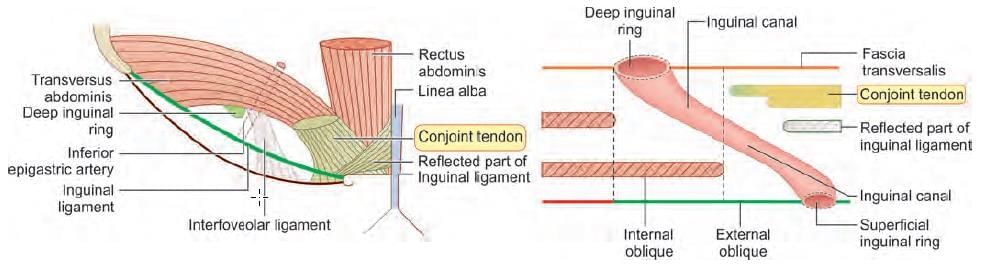

Hernia lying medial to inferior epigastric artery and superior to pubic tubercle, occurs due to weakness in: (NEET-PG 2023)

Superior boundary of the arrow marked structure is: (INI-CET July 2021)